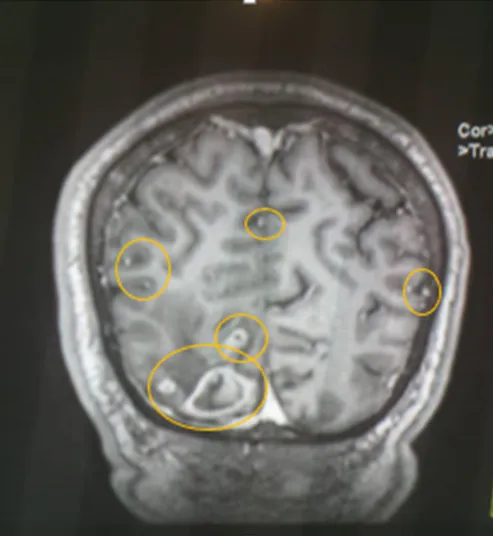

• En vista de compromiso Neurológico se solicita Resonancia Magnética Cerebral donde se evidencia:

Conclusiones del estudio Rx

En el presente estudio se observan múltiples imágenes quísticas de neurocisticercosis, de diferentes tamaños y en diferentes fases, vesicular, nodular y calcificadas, siendo la de gran tamaño la de localización parieto occipital derecha, con importante edema perilesional que genera efecto de masa desplazando estructuras y comprimiendo ventrículos.

En vistas de hallazgo de estudio de neuroimagen, es valorado por el ser servicio de neurología, quienes concuerdan que dichas lesiones son características de Neurocisticercosis, en sus diferentes etapas, siendo la de mayor tamaño de localización parieto occipital derecha en fase calcificada pero con importante edema perilesional.